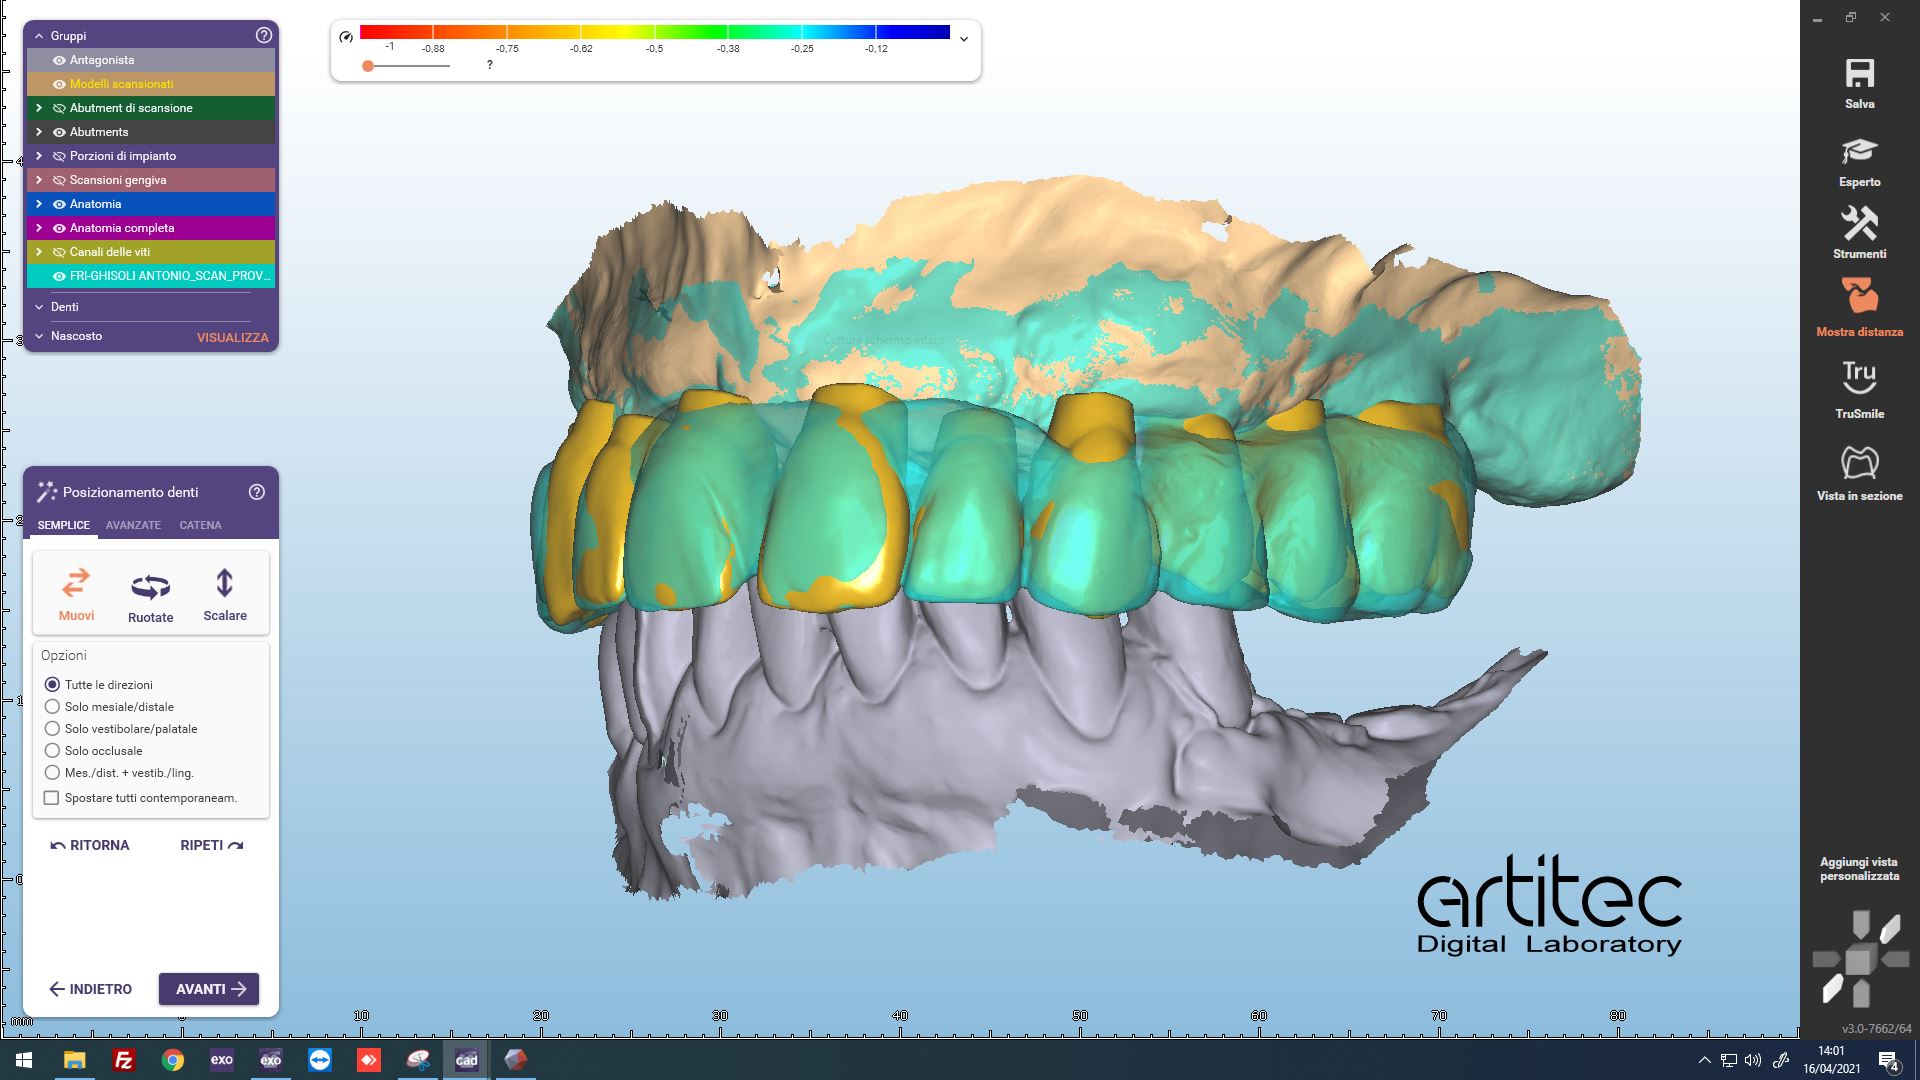

Fig. 5 Posizionamento anatomie dalle informazioni della scansione del provvisorio

Fig. 6 Posizionamento anatomie CAD/CAM